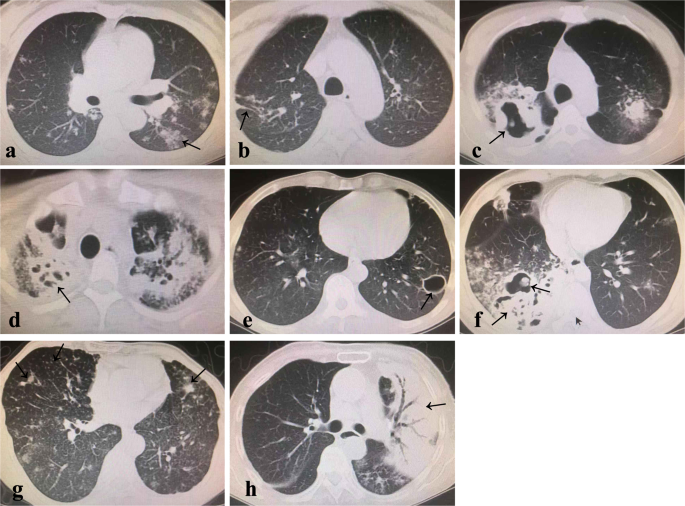

(1) Chest CT was firstly reported by an imaging technician, and then another imaging technician checked, and finally a tuberculosis clinician judged again after fetching the data. If the results were still inconsistent, the expert group would re-read the image, and reached a consensus after discussion. (2) Image classification criterion27 of the chest CT was as follows: Stage 1 (minimal/mild): Mild to moderately dense lesions with no cavity and involving only part of one lung or both lungs, The entire range is smaller than the volume of the lung on one side above the junction between the second rib and the sternum. Stage 2 (moderate): Lesions were in one lung or both lungs, but the entire range did not exceed any of the following: ① Small or moderate diffuse lesions with a distribution that did not exceed the entire area of one lung. if lesions were in both lungs, the total area of the lesions did not exceed the area of one lung; ② Highly dense fusion lesions that did not exceed one-third of the volume of a single lung; ③ When there were cavities, the largest diameter of the cavity was less than 4 cm. Stage 3 (advanced): Cases in which the lesion range exceeded the described above for moderate lesions. (3) Lesion types (Fig. 3): Patch-like shadow: the high-density shadow can be seen in the lung, which is patchy and cloudy, with irregular shape, uneven density, and blurred or clear edges. Filamaentous shadow: the lung has a high density shadow that changes in the shape of stripe, similar to the shape of one or more tiny chains. Speckled nodular shadow: uniform/uneven distribution, uniform/uneven size, uniform/uneven density, rounded or oval miliary nodular shadow with a diameter of 1-3 mm; calcification in some lesions, which could be complicated with hilar and mediastinal lymph nodes swelling. Cheese-like lesion n: it is manifested as the lobar consolidation, with multiple small voids inside, as well as disseminated pulmonary tuberculosis along the airway.

Patch-like shadow (a), filamentous shadow (b), thick-walled cavity (c), mouth-eaten cavity (d), thin-walled cavity (e), thick wall + mixed mouth-eaten mixed cavity (f), speckled nodular shadow (g), cheese-like lesion (h).

(4) Cavity types (Fig. 3): Cavity wall ≥3 mm was thick wall, and cavity wall <3 mm was thin wall. A plurality of bright areas of different sizes and irregular shapes in the lobi pulmonis and the segment sheet-like real image, and no clear wall was mouth-eaten cavity, and more than two types of cavities coexisted as mixed cavity.